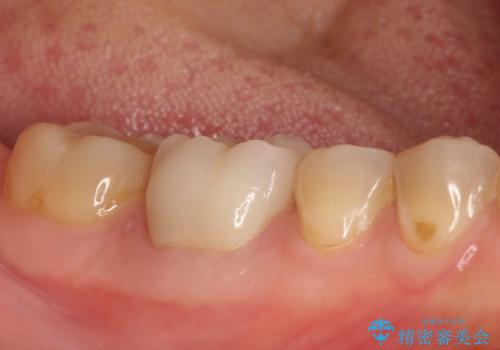

【精密根管治療】間違った根管形成→パフォレーションリペアによる修復

- 他院で根管治療を行なっていたが、以下のような不信感があり転院されてきた患者様です。

・ラバーダムを使用しない

・薬の交換と言って何回も通院しており、いつまで続くかわからない。

根管内を見てみると、近心根は本来の根管とは違うところを削られて髄床底でパーフォレーションを起こしていました。

また、遠心根でも本来の根管とは逸脱した方向に根管形成されていましたが、修正し充填を行っています。